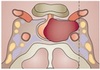

a, Caudate nucleus; b, Putamen; c, Globus pallidus (External segment); d, Globus pallidus (Internal segment); e, Substantia innominate; - nucleus of meynert. Produces acetylcholine f, Internal capsule; g, External capsule; h, Extreme capsule; i, Claustrum; - involved in behaviour j, Amygdala; k, Hippocampus; l, Thalamus.

295

a, Anterior nucleus; b, Ventral anterior nucleus; c, Lateral dorsal nucleus; d, Ventral lateral nucleus (oral part); e, Ventral lateral nucleus (caudal part); f, Lateral posterior nucleus; g, Ventral posterolateral and ventral posteromedial nuclei; h, Dorsomedial nucleus (Magnocellular); i, Dorsomedial nucleus (Parvicellular); j, Pulvinar; k, Medial geniculate nucleus; l, Lateral geniculate nucleus.

296

a, Edinger-Westphal nucleus; b, Oculomotor nucleus; c, Trochlear nucleus; d, Trigeminal motor nucleus; e, Abducens nucleus; f, Facial motor nucleus; g, Salivatory nuclei (superior); h, Salivatory nuclei (inferior); i, Dorsal vagal motor nucleus; j, Nucleus ambiguous; k, Hypoglossal nucleus; l, Trigeminal mesencephalic nucleus; m, Trigeminal main sensory nucleus; n, Trigeminal spinal nucleus; o, Dorsal cochlear nucleus; p, Nucleus of tractus solitaries.

297

a, Anterior medullary velum; b, Middle cerebellar peduncle; c, Median sulcus of rhomboid fossa; d, Striae medullares; e, Foramen of Luschka; f, Hypoglossal trigone; g, Vagal trigone; h, Tela choroidea (cut edge); i, Gracile tubercle; j, Superior cerebellar peduncle; k, Medial eminence of fourth ventricle; l, Facial colliculus; m, Superior fovea; n, Vestibular area; o, Lateral recess; p, Sulcus limitans; q, Restiform body; r, Inferior fovea; s, Cuneate tubercle.